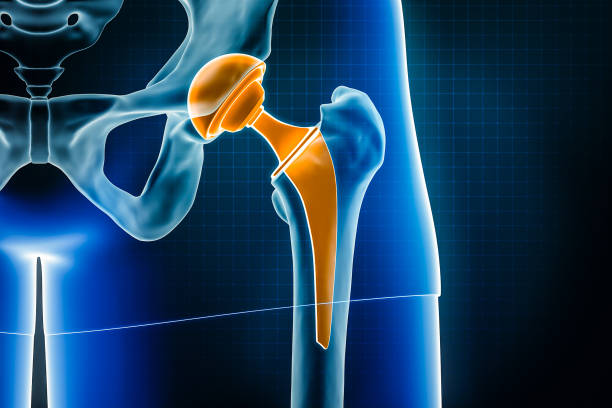

Advanced Joint Replacement Surgery in Noida

When it comes to joint replacement surgery, ShardaCare – Healthcity is your trusted partner. We offer expert Knee Replacement Surgery, Hip Replacement Surgery, and Ankle Replacement Surgery in Noida to help you regain your mobility and reduce pain. Our highly skilled surgeons use advanced techniques to perform joint replacements, minimising downtime and accelerating recovery.

From joint replacements to fracture repairs and spinal fusion, orthopaedic surgery addresses a range of musculoskeletal conditions, restoring function and mobility.